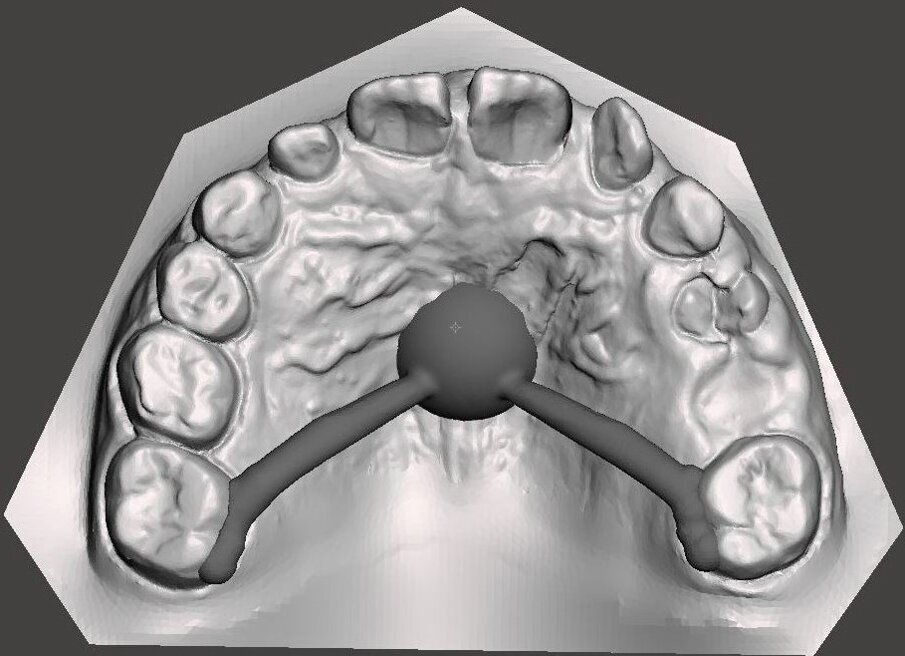

Il dispositivo customizzato e prodotto tramite laser sinterizzazione (Fig. 23), viene cementato su “E” e riattivato periodicamente. Dopo la fase di espansione e stabilizzazione (Fig. 24), vengono ottenuti dei nuovi modelli virtuali per la progettazione (Fig. 25) e produzione (Fig. 26) tramite fresatura di una barra di Nance in Trilor® (Bioloren, Seregno, Italia). Alessandro, una volta cementata la barra di Nance (Fig. 27), viene sottoposto ad estrazione anticipata dei canini (5.3-6.3) e dei primi molari decidui (5.4-6.4).

Fig. 25_Progetto CAD della Nance in Trilor.